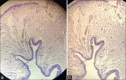

Genitourinary tract arteriovenous malformations are extremely rare. Most of the lesions are found either in the kidney or urinary bladder. So far, to the best of our knowledge, only five cases of arteriovenous malformation of the ureter have been reported in the literature. Here, we present, a young male, clinically presented with pain in the left flank with no other significant history. On radiological evaluation found to have left hydroureteronephrosis with stricture of the left distal ureter at the level of iliac vessel crossing. Urine routine, cytology, and cystoscopy were unremarkable. Left retrograde pyelogram showed distal ureteric stricture. Patient underwent excision of left distal ureteric stricture segment and ureteric reimplantation with psoas hitch. Histopathological examination revealed the features of arteriovenous malformation of the left ureter. The patient is asymptomatic and has no recurrence on follow-up until 12 weeks after surgery.